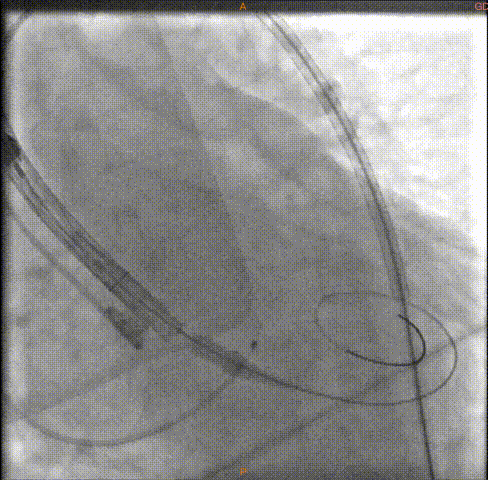

瓣膜定位

瓣膜释放